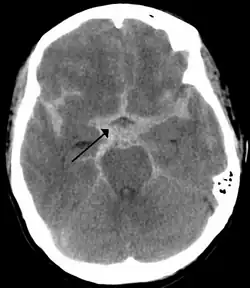

| CT scan of the brain showing subarachnoid hemorrhage as a white area in the center (marked by the arrow) and stretching into the sulci to either side | |

The modality of choice is computed tomography (CT scan), without contrast, of the brain. This has a high sensitivity and will correctly identify 98.7% of cases within six hours of the onset of symptoms.[31] A CT scan can rule out the diagnosis in someone with a normal neurological exam if done within six hours.[32] Its efficacy declines thereafter,[1] and magnetic resonance imaging (MRI) is more sensitive than CT after several days.[4]